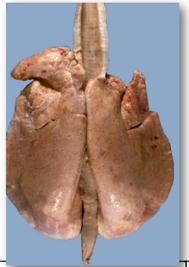

Pasteurella pnuemonia/septicaemia in a lamb

This a fibrinous pneumonia.

* Affected parts: usually the cranioventral lung regions. They feel consolidated/hard and not spongy.